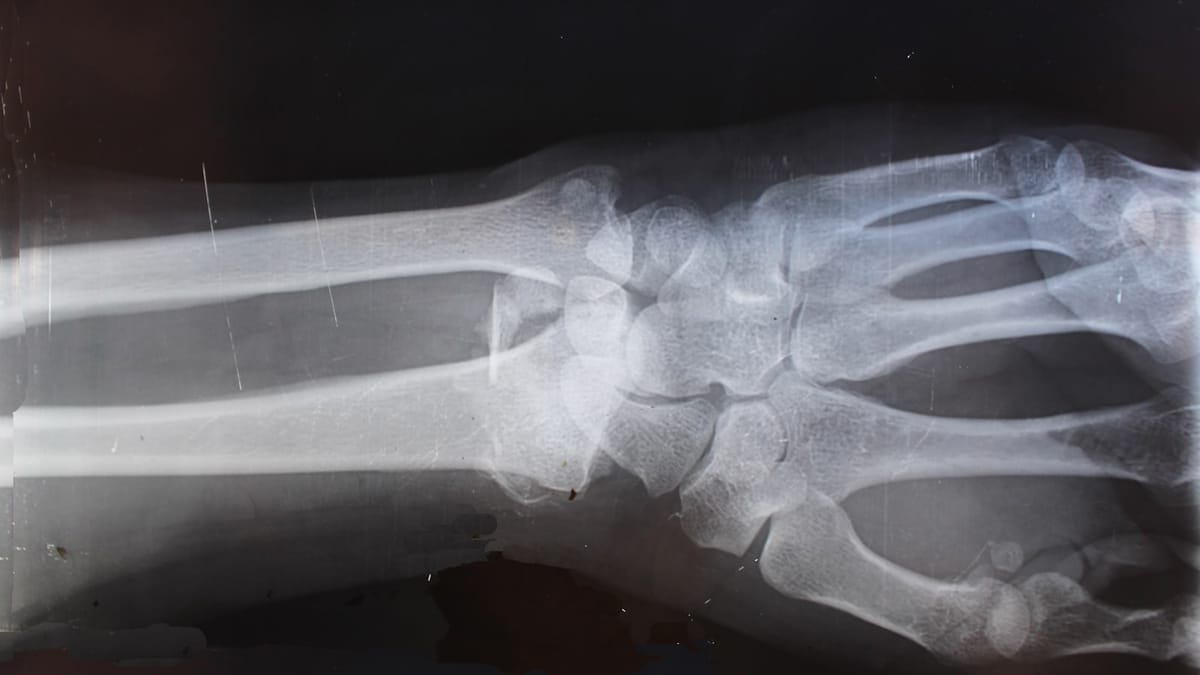

Nedávny prípad v Číne ukázal, že aj zdanlivo malá výška môže mať fatálne následky. Muž menom Zhang zomrel po páde do priekopy z výšky len 1,2 metra. Prípad vyvoláva otázku: Ako mohol taký krátky pád viesť k smrti? Forenzné vyšetrovanie odhalilo znepokojivé detaily a poukazuje na to, že vnímanie bezpečnosti pri pádoch z malých výšok môže byť veľmi zavádzajúce.